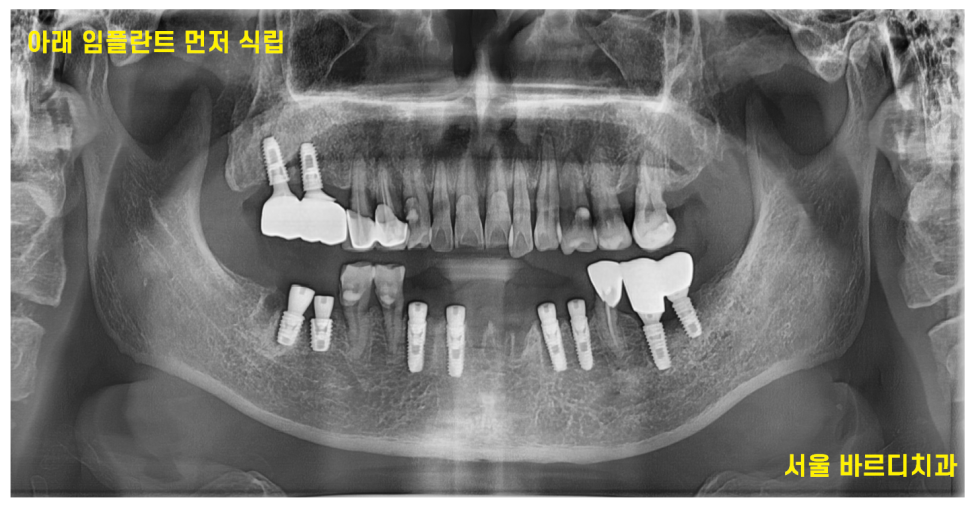

<수술 과정 1>

240508

발치 후 난이도가 상대적으로 간단한 아래 임플란트 먼저 6개 식립

상악 임플란트의 경우 뼈 자체도 약하고

상악동이라는 구조물을 조심해야하기 때문에

아래보다는 난이도가 있는 편입니다.